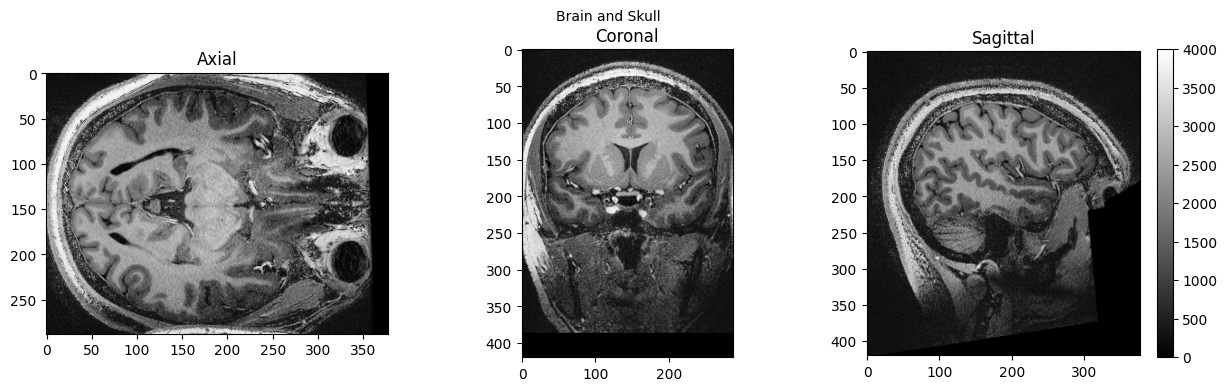

from nipype.interfaces import fsl

from nipype.interfaces import afni

btr = fsl.BET()

btr.inputs.in_file = './sub-01_ses-01_7T_T1w_defaced.nii'

btr.inputs.frac = 0.4

btr.inputs.out_file = './sub-01_ses-01_7T_T1w_defaced_brain.nii'

res = btr.run()

brain_full = nib.load('./sub-01_ses-01_7T_T1w_defaced.nii').get_fdata()

brain = nib.load('./sub-01_ses-01_7T_T1w_defaced_brain.nii.gz').get_fdata()

view_slices_3d(brain_full, slice_nbr=230, vmin=0, vmax=4000, title='Brain and Skull')

view_slices_3d(brain, slice_nbr=230, vmin=0, vmax=4000, title='Brain Extracted')